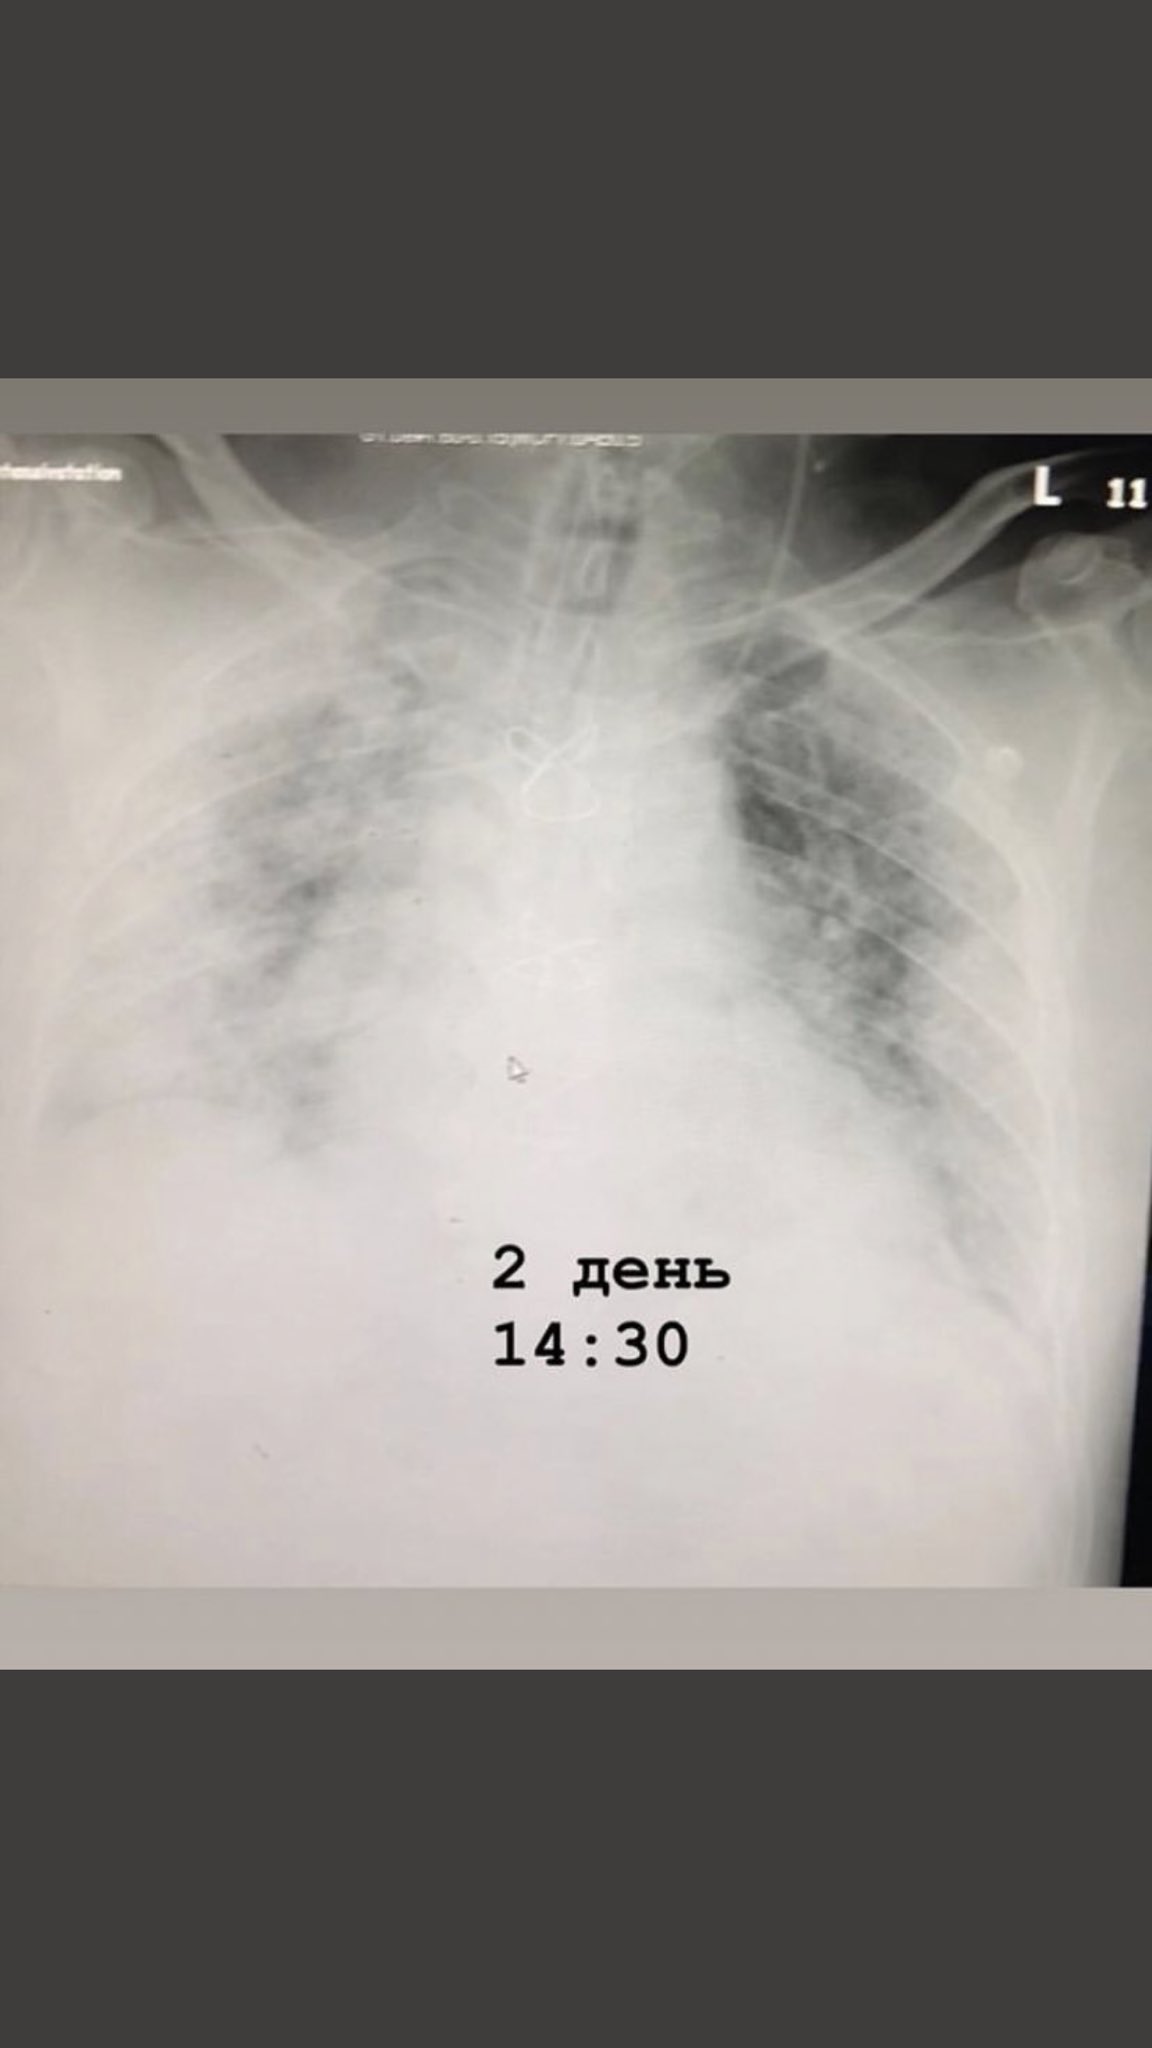

Поражение легких является одним из основных симптомов коронавируса (COVID-19). В данной статье представлены фото рентгеновских снимков, которые позволяют визуально оценить состояние легких при этом заболевании.

На фотографиях рентгеновских снимков видно, как вирус воздействует на легочную ткань. Характерные признаки поражения легких включают пятна, инфильтраты и наличие жидкости внутри легочных альвеол.

Фото рентгеновских снимков помогают врачам и специалистам визуально определить степень поражения легких и принять соответствующие меры лечения и поддержки пациента.